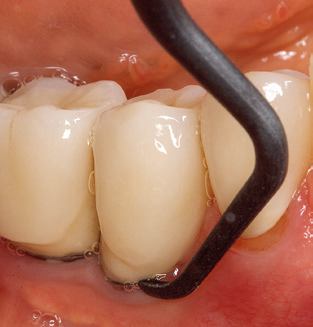

Updating the patient’s medical history is an important aspect of SPT and should occur at least once per year. It helps the dental team to identify and document any new risk factors. Especially when a patient is treated over many years, it is important to establish whether patient-specific and general health risk factors have changed. This primarily concerns a heightened risk as a result of diabetes, but other general conditions (cardiovascular disease and neoplasia) can also produce a modified risk profile as a result of the treatment performed and medication administered. Accordingly, updating the medical history as part of SPT is very important, as a modified risk profile may trigger the need to adapt the treatment interval. In the next step, it is important to afford the diagnostics due attention. Whilst instruments are a central aspect of SPT, findings and their documentation must never be neglected. The periodontological findings are essential for a good diagnosis; increases in the pocket depths and the BOP index are clear indicators of advancing periodontal and peri-implant disease. As such, the team should not shy away from probing implants too, with the aim of gathering the requisite data. At the same time, it is important to use periodontal probes with millimetre markings. Metallic probes have already been used for determining pocket depths around natural teeth for decades. In the case of implants, the challenge of recording correct and reproducible pockets depths is even greater. As the discrepancy between the implant diameter and the contour of the superstructure regularly results in overcontouring of the superstructure, flexible probes which still feature millimetre markings are a sensible solution for measuring pocket depths around implants (e.g., Colorvue Kit PCV11KIT6, Hu­Friedy; Fig. 4).

Fig. 4: Flexible probes with millimetre markings are recommended for the probing of dental implants (e.g. Colorvue Kit PCV11KIT6, Hu­Friedy). – Fig. 5a and b: A straight working tip (1P, W&H Dentalwerk Bürmoos GmbH) is a suitable instrument for use on all natural teeth. – Fig. 6: Curved working tips (3Pr/3Pl, W&H Dentalwerk Bürmoos GmbH) lend themselves to the processing of difficult-to-reach areas of the tooth and root surfaces (e.g. furcations). – Fig. 7: The tapered, hexagonal implant cleaning tip (1I, W&H Dentalwerk Bürmoos GmbH) permits atraumatic and efficient cleaning of the crown and abutment surfaces. – Fig. 8: Titanium and carbon curettes are suitable instruments for the manual cleaning of the implant surfaces.